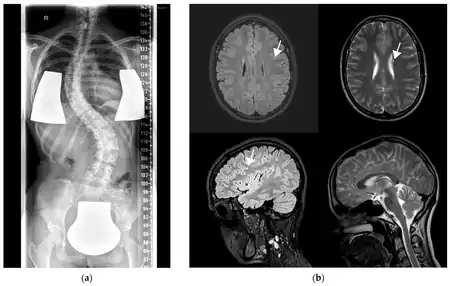

a) X-ray showing scoliosis b) MRI with left frontal FLAIR hyperintensity

GOSR2-related progressive myoclonus ataxia, also known as Progressive myoclonic epilepsy type 6 is a rare genetic type of progressive myoclonus ataxia which is characterized by progressive myoclonic epilepsy with an early onset which is associated with generalized tonic-clonic seizures, petit mal seizures, and drop attacks, variable degrees of scoliosis, areflexia, high levels of creatine kinase serum, and late-onset cognitive decline.[1][2]